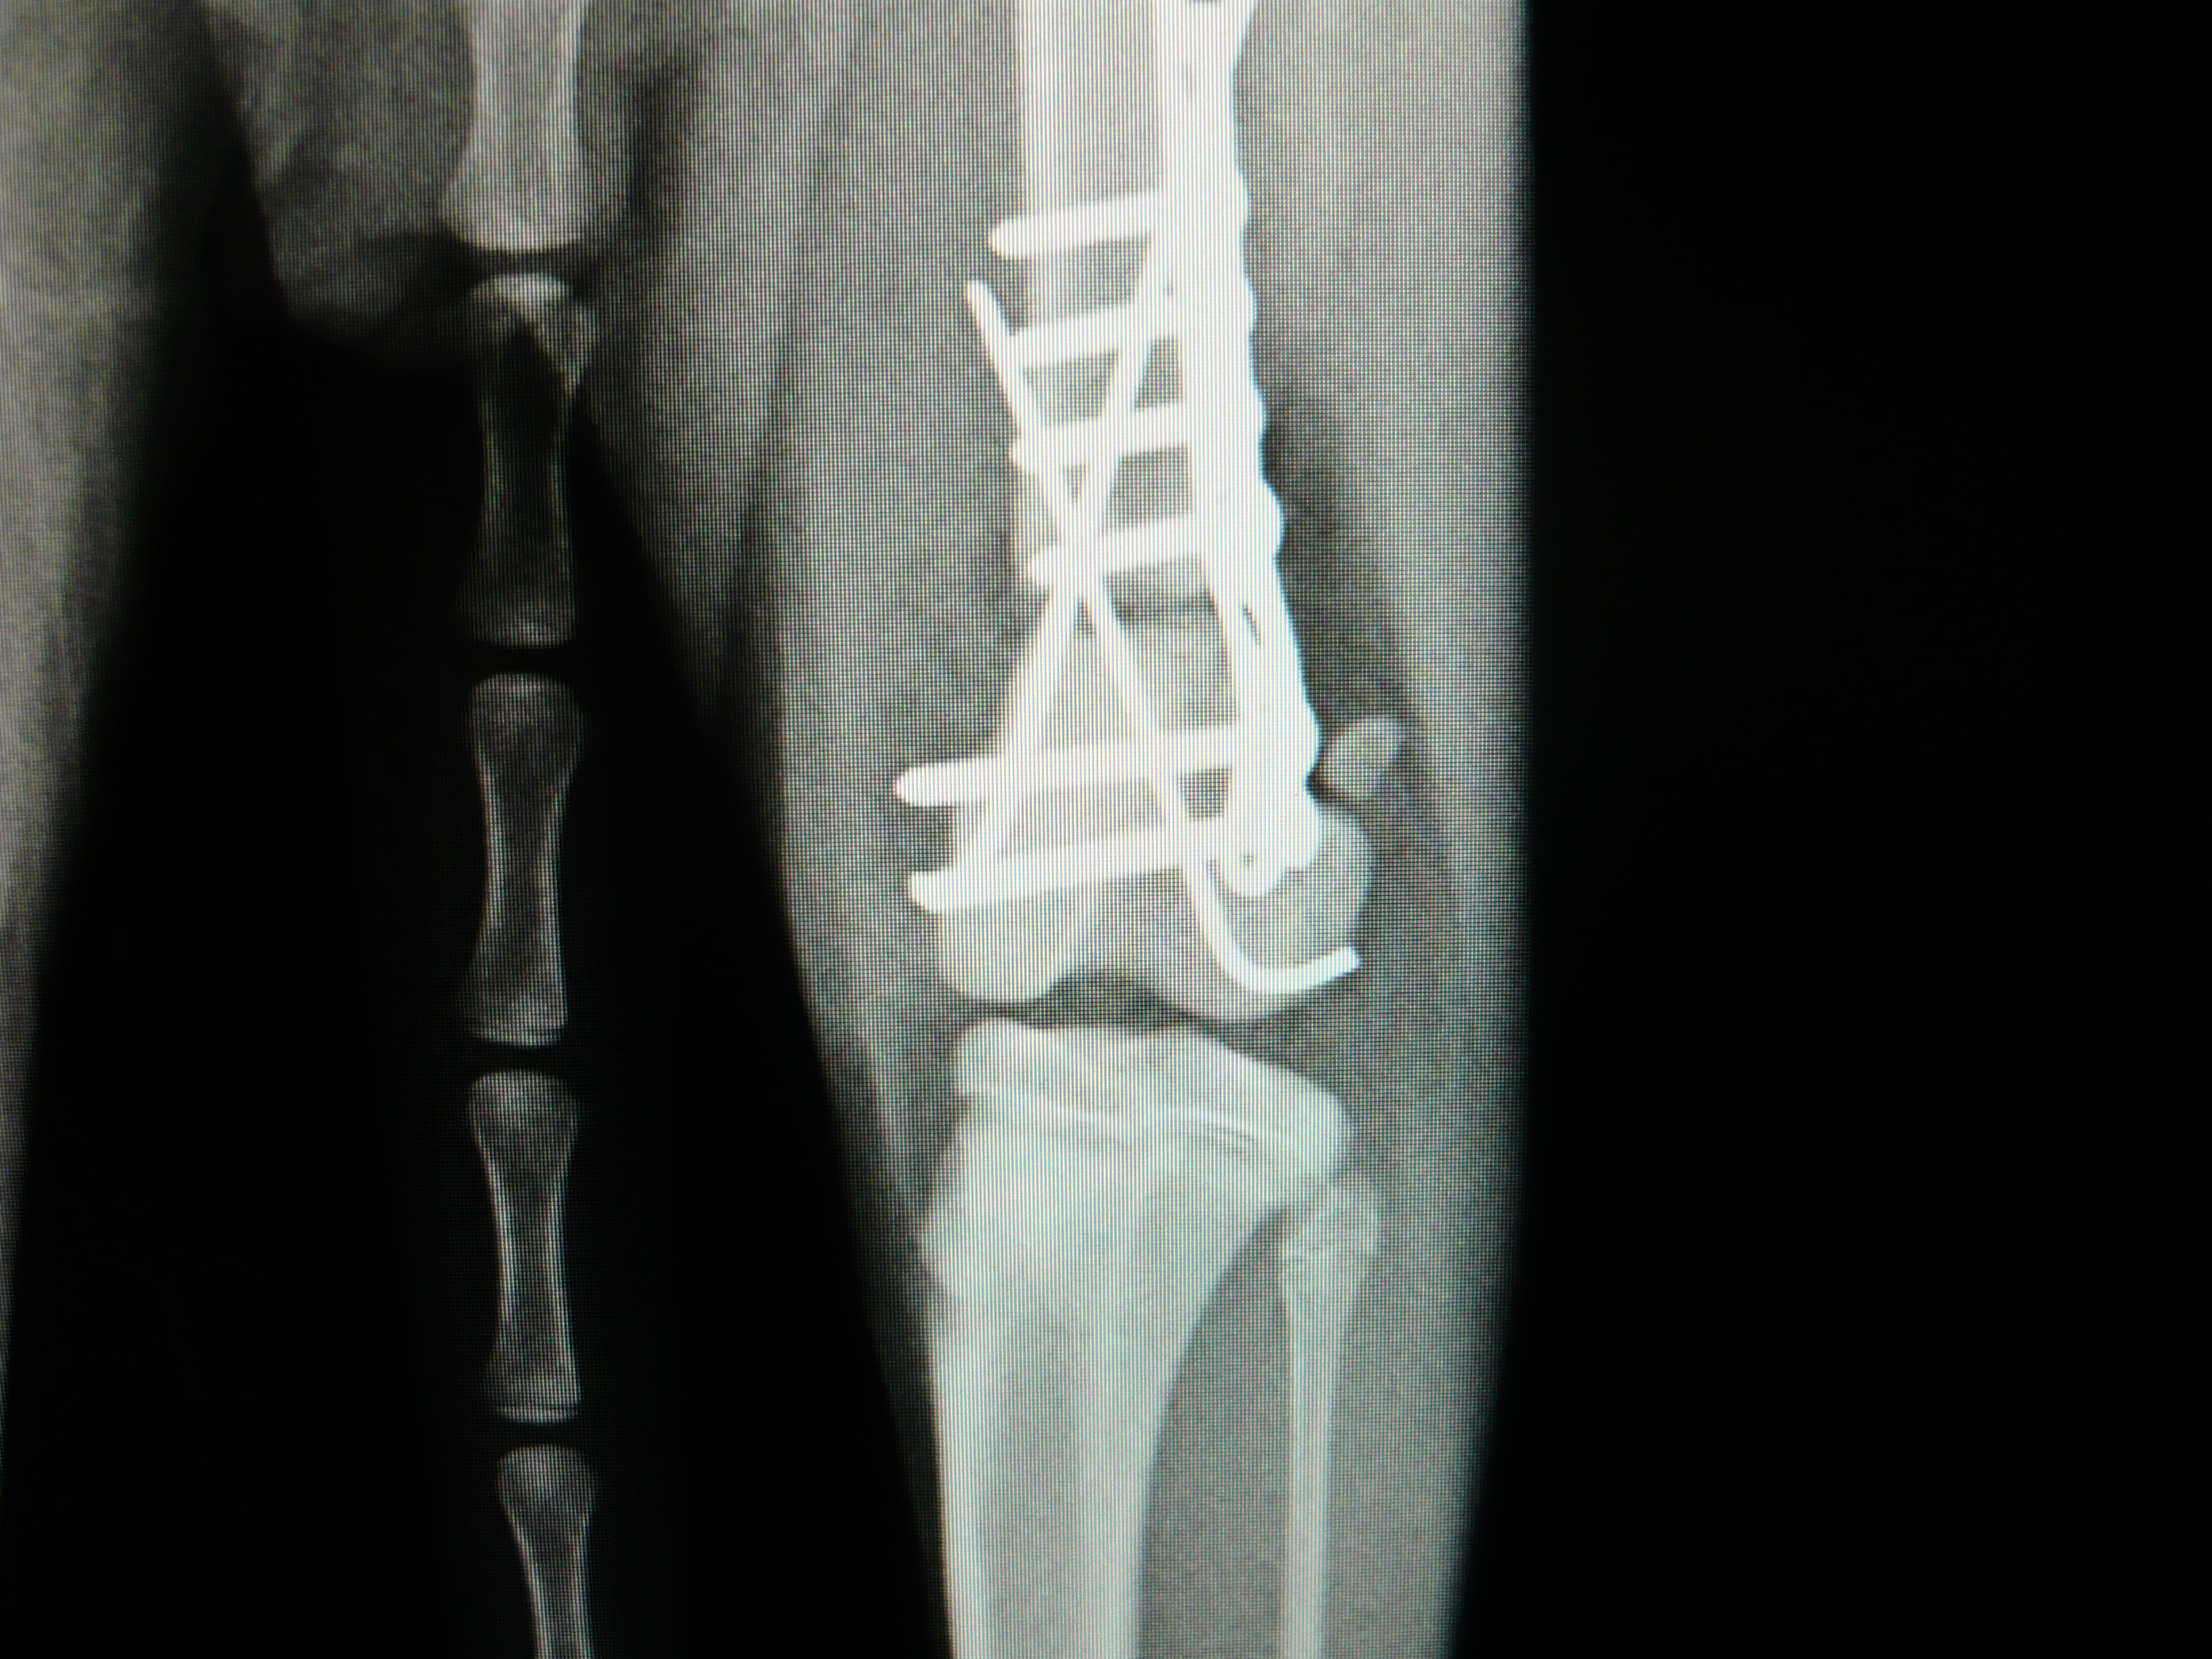

新しい医療機器(血圧計)を導入しました。

新しい医療機器(血圧計)を導入しました。 動物用非観血血圧計 Alivio BP200D (株)フクダ・エム・イー工業 体動の激しい動物の血圧測定を可能にする 高性能機器です。 高齢期に多い […]